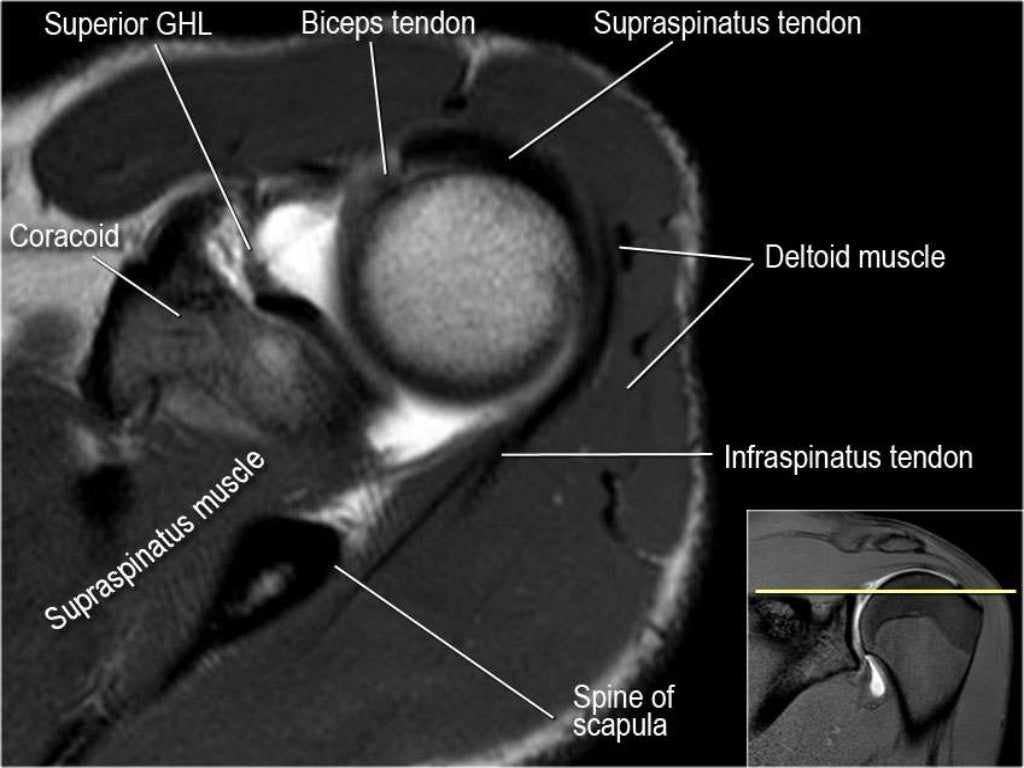

shoulder anatomy mri shoulder axial anatomy free cross sectional Shoulder Mri Images Explained Here is a comprehensive guide to understanding your shoulder mri, including if it's normal or. Learn more about what it’s for, what to expect,. Mri of the shoulder provides detailed images of structures within the shoulder joint, including bones, tendons, muscles and vessels, from any. Decode your shoulder mri report with this detailed guide, explaining essential mri terms and their. Shoulder Mri Images Explained.